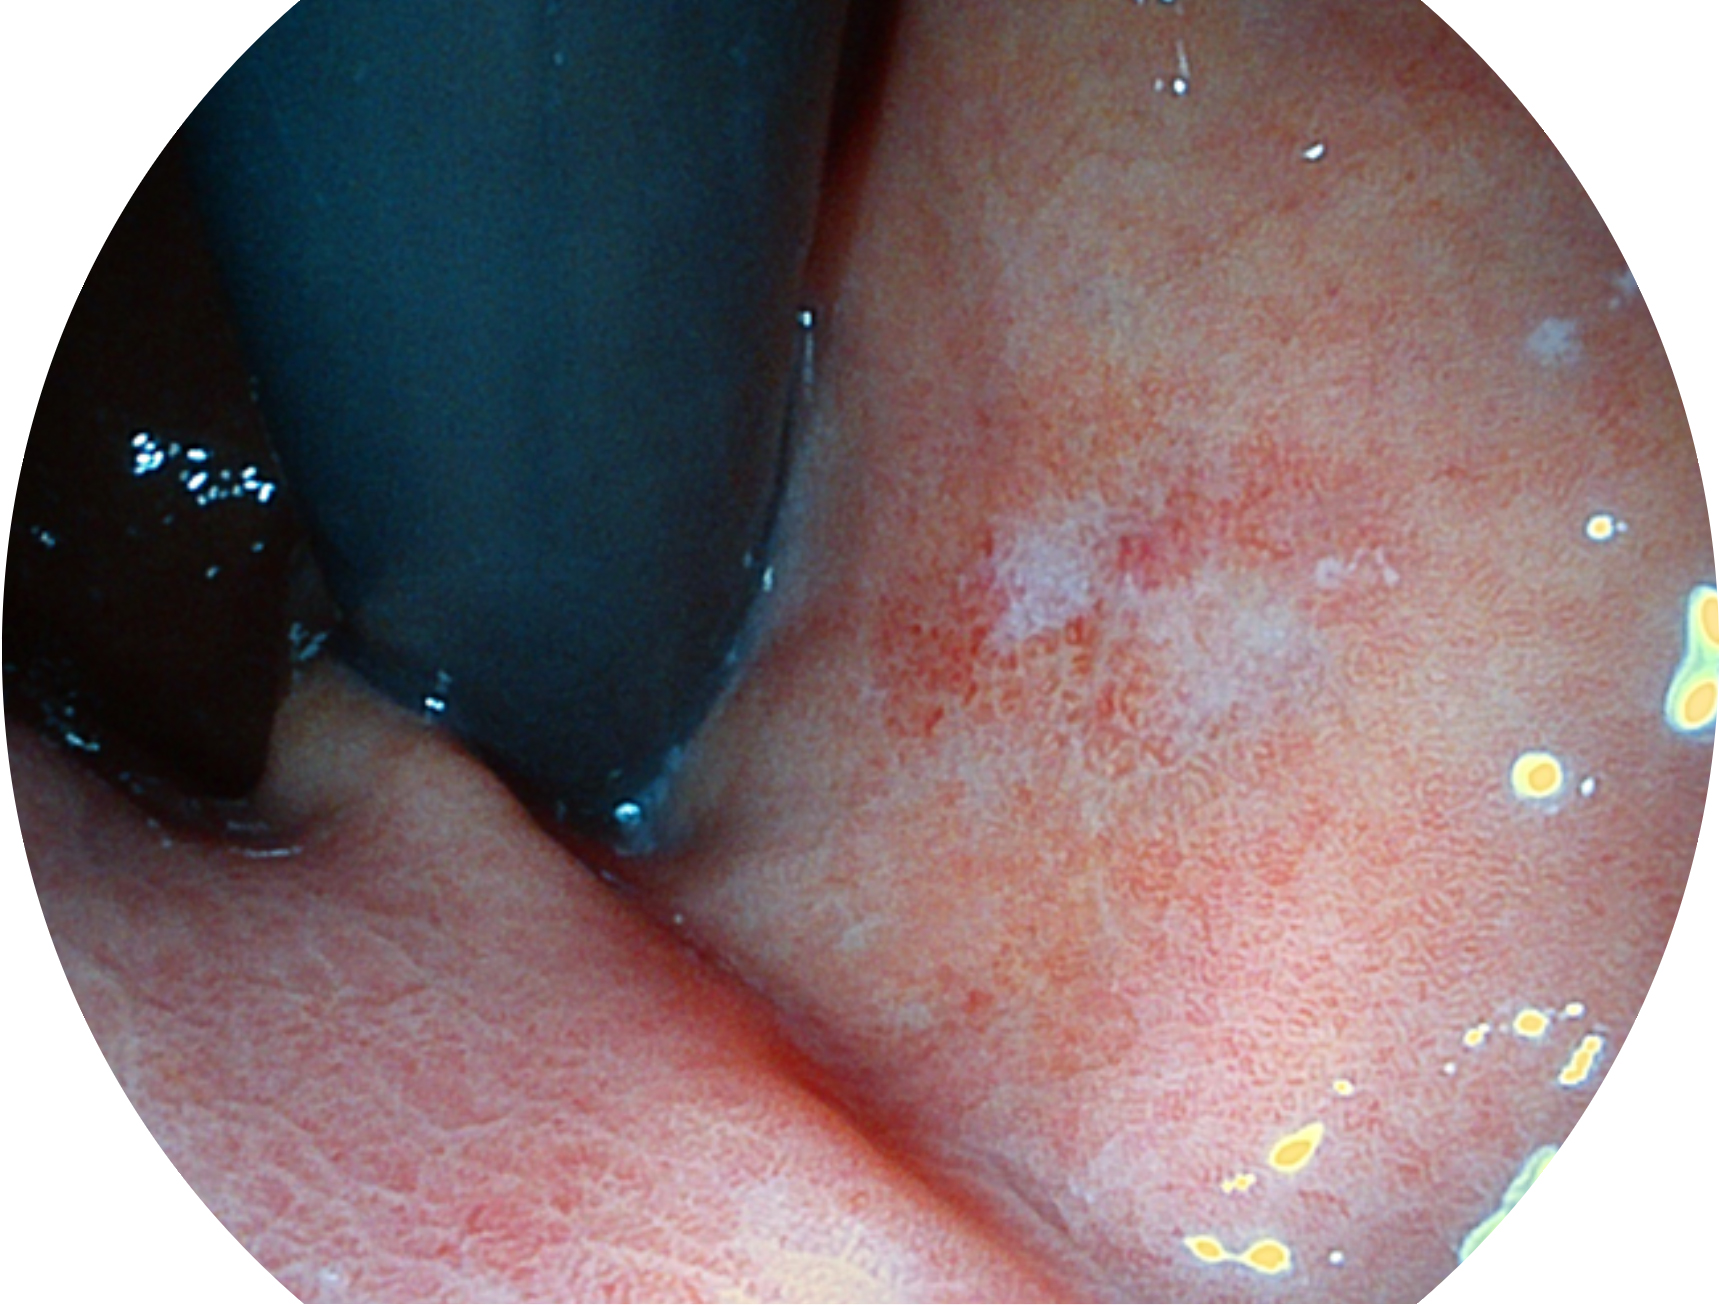

九州酷游新开发的内镜染色技术,主要是基于多波长LED 光源的开发,VLS-55Q 四波长LED 光源是由四个不同颜色的LED光按照相应照明模式所规定的特定发光比例进行合束后形成,合束后形成的照明光的光谱由红光、绿光、蓝光及蓝紫光这四个不同的波段范围构成。具有更高光谱自由度,通过光谱比例的控制,实现了聚谱成像技术,英文全称为“Spectral Focused Imaging, SFI”,缩写为“SFI”和光电复合染色成像技术,英文全称为“Versatile Intelligent Staining Technology, VIST”,缩写为“VIST”。